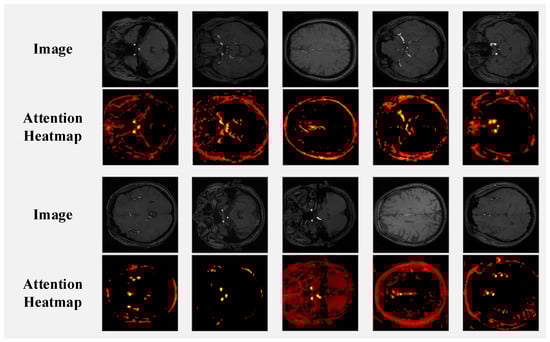

Figure 8 displays ten sets of TOF-MRA brain slices and their corresponding spatial attention heatmaps from the AttentionGate module in nnUNet-MedSAM2. The specific steps are as follows: first, we extract the attention weights from the AttentionGate module and convert them into NumPy arrays. Then, these raw attention maps are upsampled to the original image dimensions ( 640 × 640 ) using bilinear interpolation to preserve spatial relationships. Finally, for enhanced visualization, the values are normalized to [0, 1] and mapped to a red-to-orange gradient heatmap, with an empirical threshold of 0.5 to suppress background regions (values below the threshold are set to black), thereby improving the clarity of vascular structures. The heatmaps are presented in a gradient from red to orange, where higher brightness indicates greater model attention to that region, while the black background represents areas with no significant attention. Our observations reveal that the model’s high-attention regions primarily focus on cross-sections of cerebral arteries in the TOF-MRA slices. This suggests that the spatial attention mechanism enhances the model’s focus on key anatomical structures of the cerebral vasculature. By weighting feature responses in vascular regions, it improves the model’s ability to identify and distinguish cerebrovascular lesions.

Figure 8. TOF-MRA slices and their spatial attention heatmaps in the AttentionGate module.